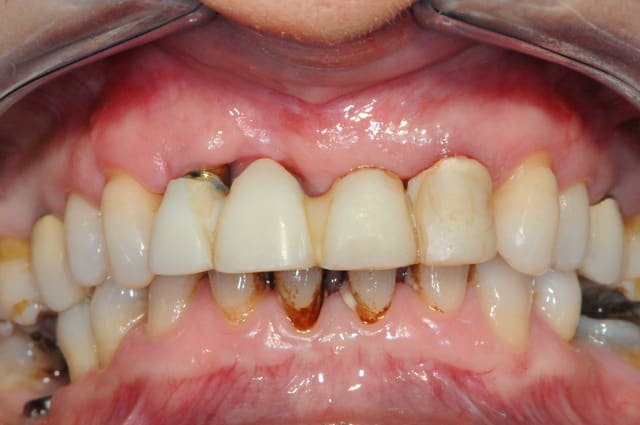

au mois d'octobre (j+5 mois), et malgré mon insistance, la patiente refusant de mettre en place les greffes muco-conjonctives pour récupérer le fiasco attendu sur 11, on débute la prothèse.

elle ne veut plus continuer, et sa reprise tabagique m'interdit une greffe. c'est vraiment dommage.

+ piliers et structure du bridge en zircone (j'adore mon proto)

suite et fin .

photos 1 et 2: jour j

photo 3: j+15